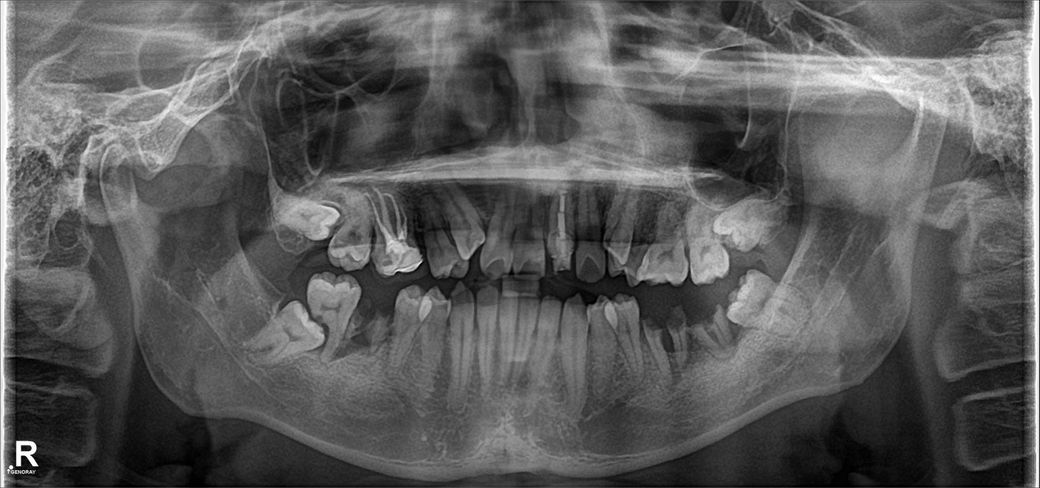

물론 정밀검사가 필요한건 알지만

의사 선생님들의 소견이 궁금합니다.

이미 대학병원은 예약을 한 상태입니다.

대학병원에 내원해서 어떤 검사를 받아야 하는지도 알려주시면 감사하겠습니다.

혹시 양악수술 건강보험이 아닌 실비 적용이 가능한 보험도 있을까요?